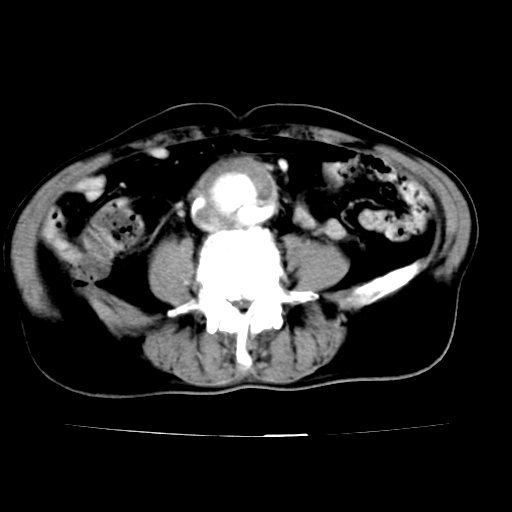

给平扫片看看血管壁钙化情况。

此病例平扫图像已发,请大家看看!

腹主动脉分叉处真性动脉瘤,附壁血栓形成。